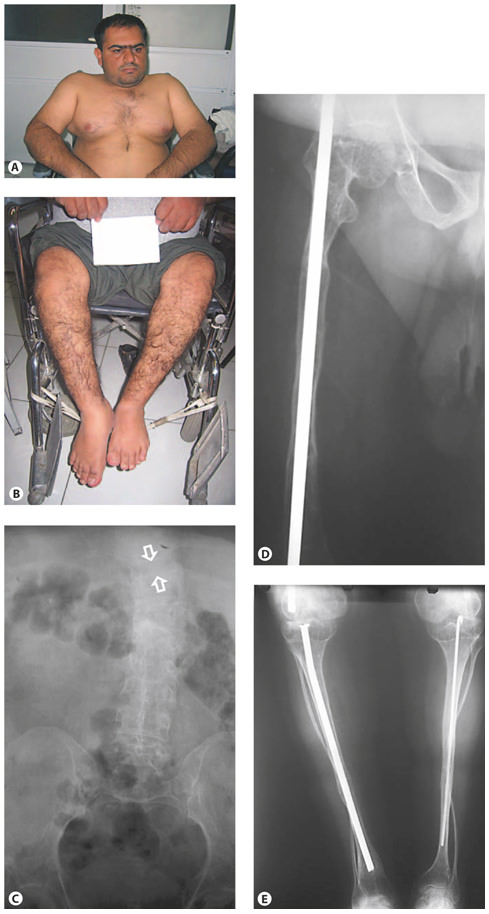

Clinical pictures and radiographs of a patient with OI type IV. A, B White sclerae, muscular upper extremities, wheelchair bound. C AP radiograph of the abdomen, of poor quality, shows a compression fracture of T10 (between arrows). D, E Radiographs of the lower extremities show reduced bone density and thin tibia shafts with both fibula being very thin and tortuous. Intramedullary rods are in position. Clinical synopsis: A 33-year-old Iranian man consulted a clinical geneticist when his wife was pregnant as he wanted to be informed about the chance of recurrence of OI in his unborn child. His height and head circumference are, respectively, 145 cm (–5.5 SD) and 57 cm (–0.5 SD). He claims he has had multiple fractures first occurring at 2 years of age. Unfortunately, no documented medical history is available. His sclerae are greyish. No hearing loss or DI is present. His father and sister were also known to be affected with OI. MLPA analysis of the COL1A1 gene showed a partial deletion of COL1A1(exon 6–51).